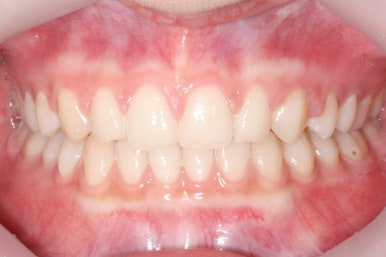

마무리 때의 사진입니다.

윗니만 부분교정하였지만 교합에도 이상 없이 매복되었던 송곳니는 매우 잘 위치를 잡았습니다.

송곳니 부위는 다시 틀어지지 않게 하기 위해 유지철사를 붙여주었습니다.

총 치료기간은 20개월 소요 되었습니다.

부산매복치아교정 상악 부분교정을 통해 매복치를 교정해준 이번 치료의 전후사진 비교입니다.

썩은 유치 대신 영구치 송곳니는 매우 자연스럽게 위치되었습니다. 아랫니는 교정하지 않았기 때문에 약간 삐뚠 느낌은 남아있지만 맞물림은 크게 문제가 없게 마무리 되었습니다.